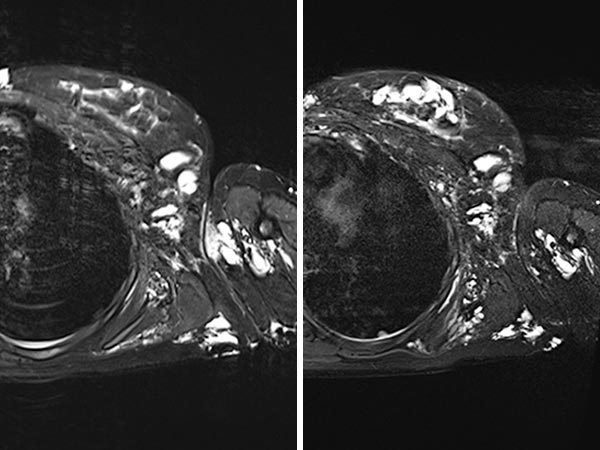

The same MRI (T2-weighted with fat suppression; now coronal plane) before (left) and after (right) bleomycin electrosclerotherapy. Again, it can be seen that the treated parts of the lymphatic malformation are occluded, but the remaining untreated parts are unchanged.